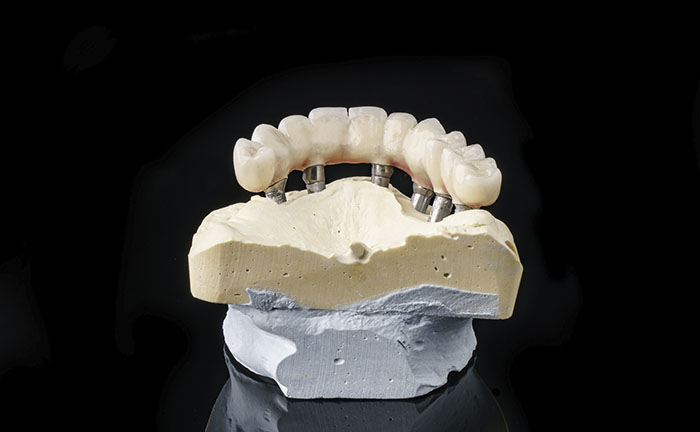

6 dental implants

6 abutments

12 resin crowns (fixed teeth)

Implantology All on 6